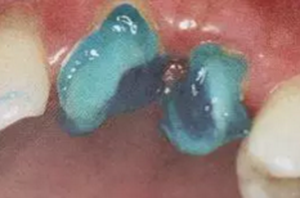

(沖洗預(yù)備根管)

應(yīng)選擇沖洗預(yù)備根管,防止牙膠及封閉劑粘連附著于根管壁形成第二層玷污層(根管治療時(shí)形成的玷污層稱為第一玷污層),利于樹脂水門汀與根管牙本質(zhì)的粘接。